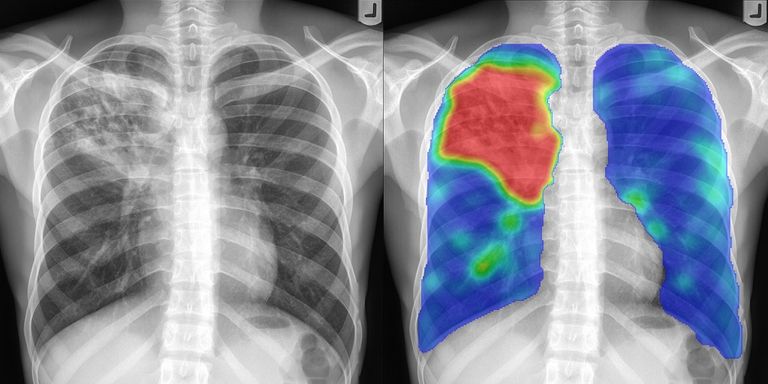

We're excited to help you learn how to analyze X-ray images to spot hidden or ingested items like drugs, weapons, and electronic devices. By the end of this course, you'll have the knowledge and practical skills you need to effectively use X-ray equipment and interpret the images you capture.

• Principles of X-ray Image Analysis

• Image Analysis

• Examples with Real Prohibited Objects